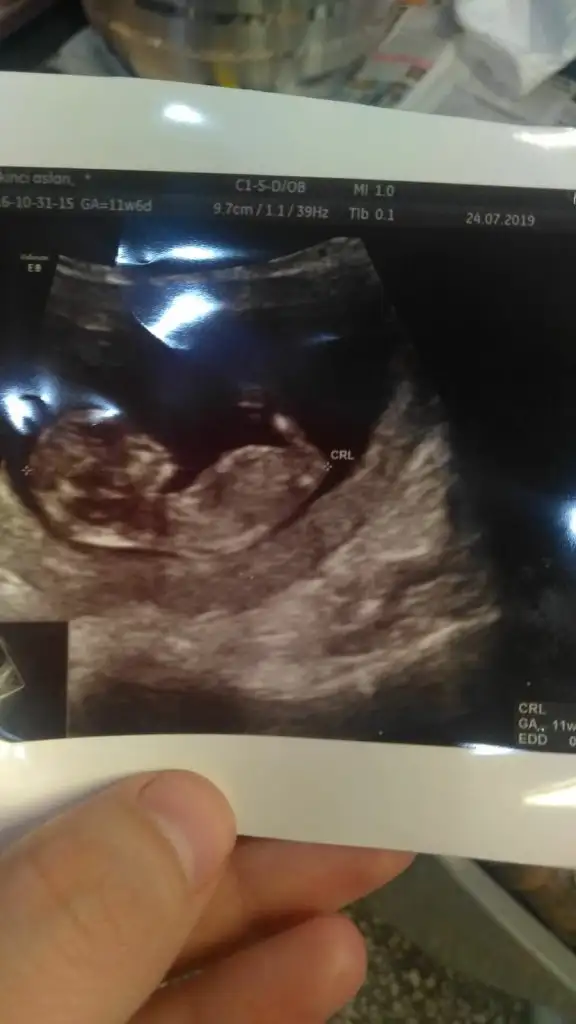

Kizlar 11+6 günlük sizce cinsiyeti nedir yorumlayabilen var mi

ikra meyra sence cinsiyet nedir😊